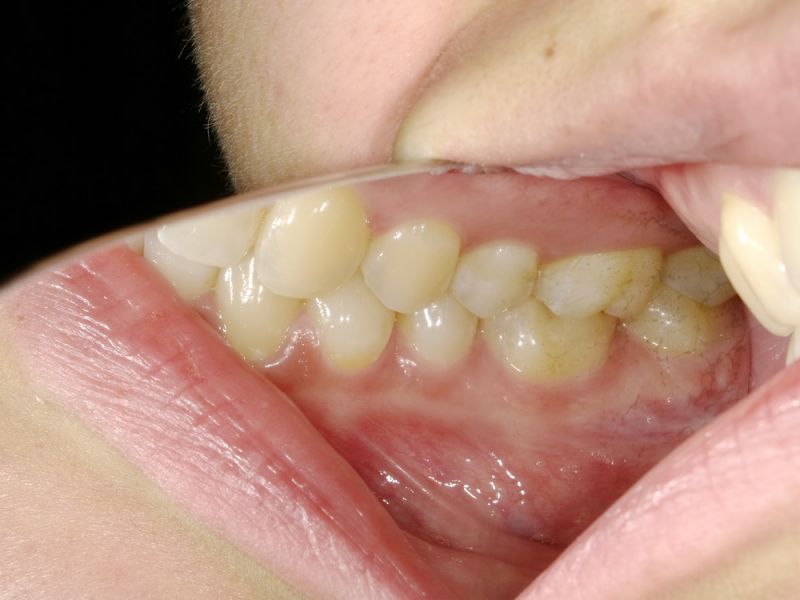

Es bestehen vorrangig Beschwerden im Berech des Halses hinter und unter dem linken Unterkieferwinkel und im Bereich des linken Ohres. Weiterhin auch im rechten Schläfenbereich nach unten hinten ausstrahlend.

Der Biss gesucht wird, der Biss passe nicht, seit ein paar Jahren

Zähneknirschen/pressen